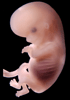

Carnegie Stage 23 (56 post-ovulatory days)

Most embryos at stage 23 are approximately 56-57 postovulatory days old and measure 23-32 mm in length. Distinguishing criteria for this stage include fusion of the eyelids at the medial and lateral margins, clear distinction of the subdivisions of the upper and lower limbs, the forearms appear at or above the level of the shoulders, the superficial vascular plexus of the head is very close to the vertex, and the external genitalia are well developed but not always sufficiently to distinguish the embryo's sex.

(NOTE: These specimens are late stage 23.)